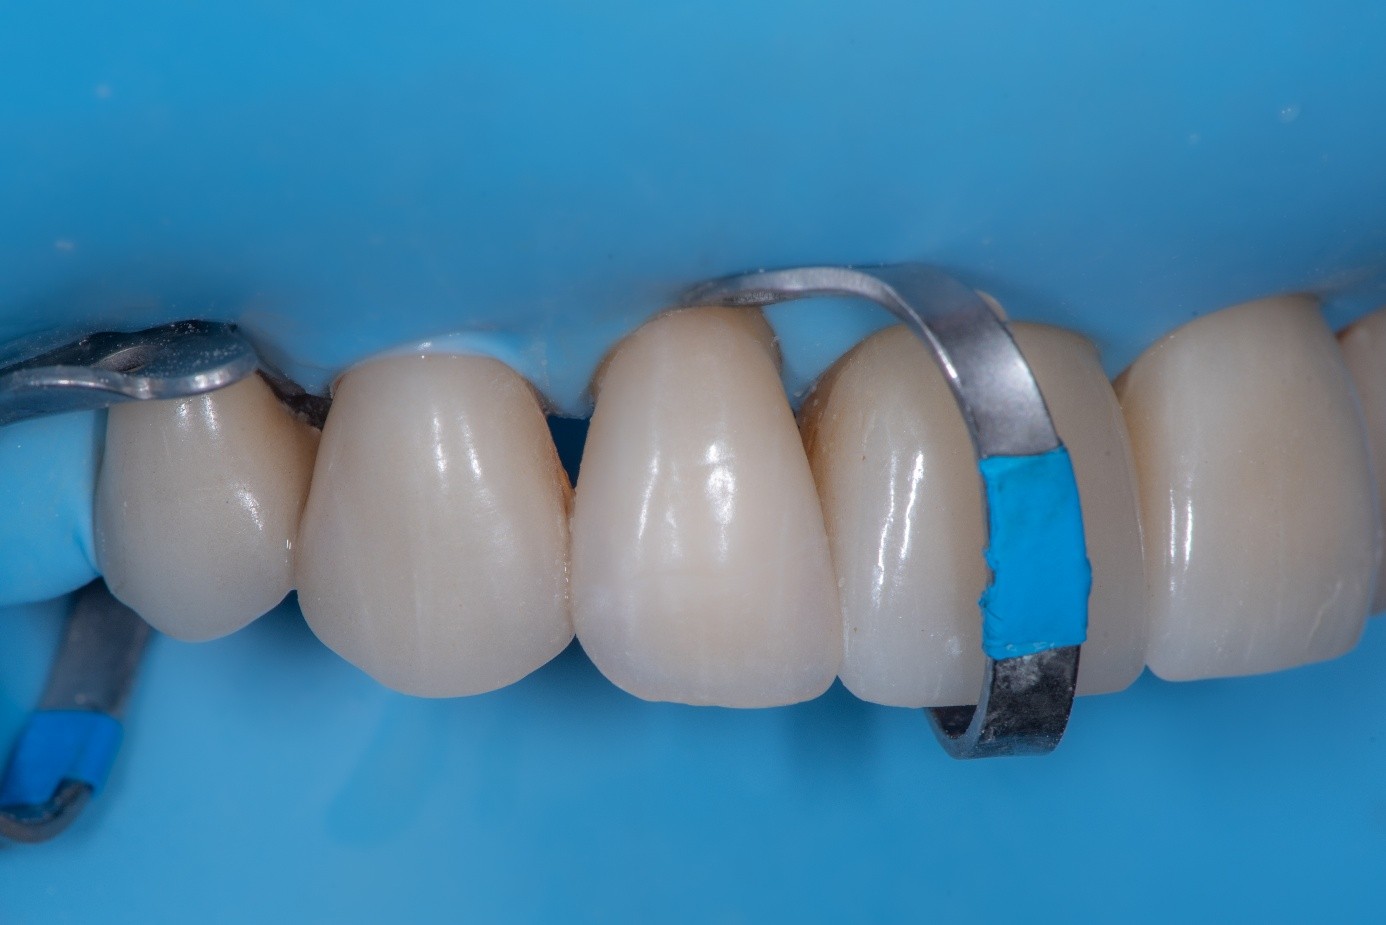

The internal surface of the zirconia crown was first air-abraded with aluminum oxide to remove residual cement and increase micromechanical retention (Figure 29).11 After cleaning, an MDP-containing ceramic primer was applied to the intaglio surface to enhance chemical bonding to zirconia.12 An adhesive was then applied but left unpolymerized to improve wetting before cementation.

Intraorally, absolute rubber dam isolation was achieved to ensure a contamination-free environment (Figure 30). The prepared tooth was air-abraded with aluminum oxide to clean the surface and increase surface energy. A primer and bonding agent were applied to the tooth surface.

(30.) Intraoral view after absolute isolation with a rubber dam, showing the prepared tooth surface cleaned and roughened with sandblasting, ready for adhesive application and bonding to the crown.

Figure 30